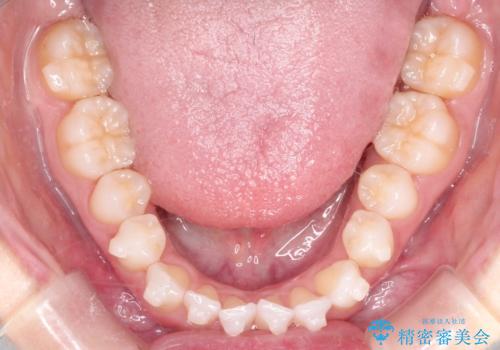

【インビザライン】前歯の凸凹をマウスピース矯正でなおしたい

- 前歯の凸凹を主訴に来院されました。

上の前歯は翼状捻転と呼ばれる状態でしたが、奥歯の遠心移動を行うことで配列スペースを確保することで綺麗に歯を並べることができました、

途中でインビザラインの使用時間が短くなってしまったため期間が予定より少し伸びましたが、1年半で満足いく結果となり患者様に喜んでいただけました。

下顎骨が右側に偏位していることにより下顎前歯の真ん中はずれています。